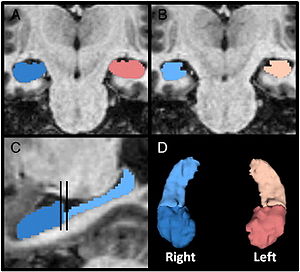

- 7.1 Atlas-guided Segmentation of Vervet Monkey Brain MRI

- 7.2 Comparison of Acute and Chronic Traumatic Brain Injury Using Semi-automatic Multimodal Segmentation of MR Volumes